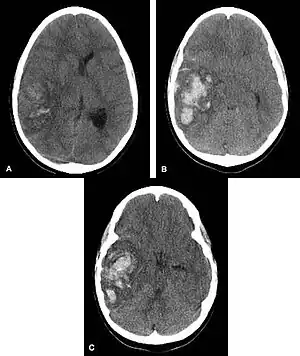

Hemorrhagic neoplasms are more complex, heterogeneous bleeds often with associated edema. These hemorrhages are related to tumor necrosis, vascular invasion and neovascularity. Glioblastomas are the most common primary malignancies to hemorrhage while thyroid, renal cell carcinoma, melanoma, and lung cancer are the most common causes of hemorrhage from metastatic disease.

Other causes of intraparenchymal hemorrhage include hemorrhagic transformation of infarction which is usually in a classic vascular distribution and is seen in approximately 24 to 48 hours following the ischemic event. This hemorrhage rarely extends into the ventricular system.